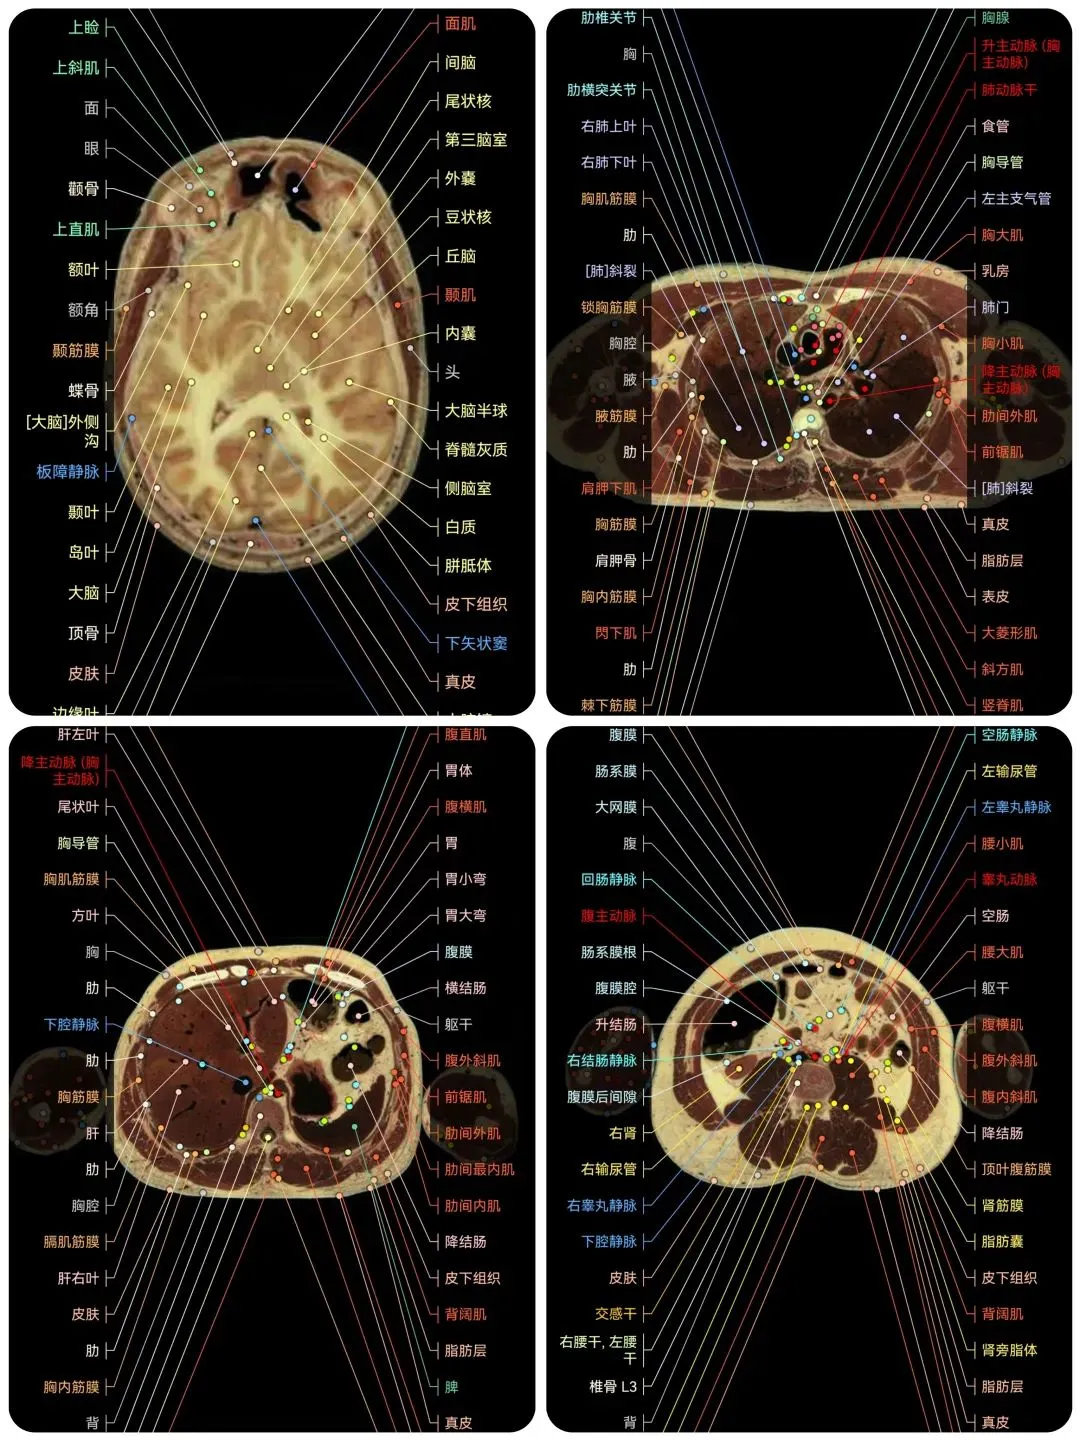

🌈这是国外引进的一款专业影像解剖学习软件。

覆盖了X光、CT、MRI、断层大体解剖、核医学、介入造影、医学插图等多个模块,覆盖全身各个系统的影像解剖(正常解剖结构,无病例),其中的解剖结构高达87万个,结构标注超精细,超高清图像,历时两年研发设计完成✅。